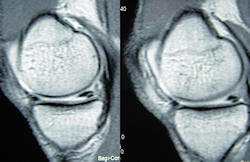

Doktorunuzun menisküs yırtığı tanısına ulaşması için önce olayın oluş şeklini anlatmanızı isteyecektir. Daha sonra dizinizi muayene ederek menisküs yırtığı bulgularını araştırır. Bu sırada yan ve çapraz bağlarınızı da muayene eder. İyi bir hikaye ve fizik muayene sonrasında menisküs yırtığı tanısı büyük ölçüde ortaya çıkar. Dizinizdeki aşınma-eskimenin miktarını değerlendirmek ve kemik yapılarda başka bir sorun olup olmadığını anlamak için doktorunuz röntgen grafileri isteyebilir. Menisküs yırtıklarının tanısını doğrulamak için son yıllarda en güvenilir yöntem diz ekleminin manyetik rezonans görüntülemesidir (MRG).